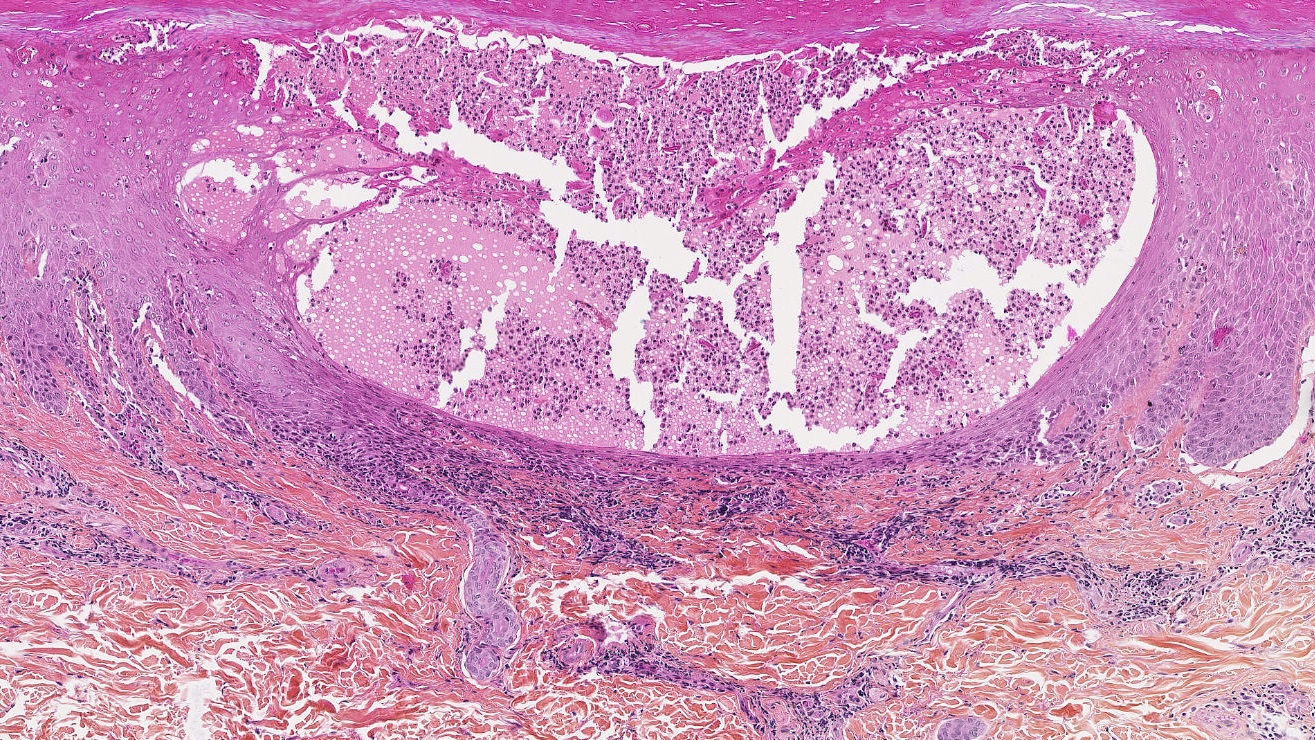

© Pr Maxime Battistella, Service d’Anatomie et de Cytologie Pathologique, Hôpital Saint-Louis-AP-HP

Pathologie auto-inflammatoire orpheline grave, le psoriasis pustuleux généralisé est caractérisé par des poussées subites sous forme de pustules non infectieuses sur la peau, souvent associée à des signes généraux (fièvre, fatigue extrême), à l’évolution imprévisible et aux complications potentiellement graves pouvant aller jusqu’au décès. La prévalence de cette pathologie est estimée entre 60 et 90 cas par million d’habitants selon les estimations les plus récentes.

Chez les patients atteints de psoriasis pustuleux généralisé porteurs d’anomalies des deux copies du gène IL36RN, l’absence d’antagoniste du récepteur ou sa présence à l’état défectueux empêche le mécanisme naturel de régulation de l’inflammation de se mettre en place, ce qui a pour conséquence un emballement de la réaction du système immunitaire marqué par une augmentation très importante des effets inflammatoires de l’interleukine 36, à l’origine des poussées de la maladie qui dépassent largement le cadre de la peau, puisque la maladie peut toucher les articulations, les poumons et le foie. Un dérèglement de la voie de l’interleukine 36 semble également jouer un rôle important chez les malades qui ne présentent pas de mutation du gène IL36RN.